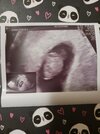

Melduję się na koniec tego długiego dnia, padam już na pysk... Mamy 1 cm pasożyta z bijącym serduszkiem 🙂 następna wizyta 19.09 i jak będzie ok to będzie karta ciąży. Przed ciążą robiłam morfologię, glukozę i tsh, na kolejną muszę mieć wyniki toxo.

Załączniki

• 20230829_185742.jpg

20230829_185742.jpg

1,2 MB · Wyświetleń: 92